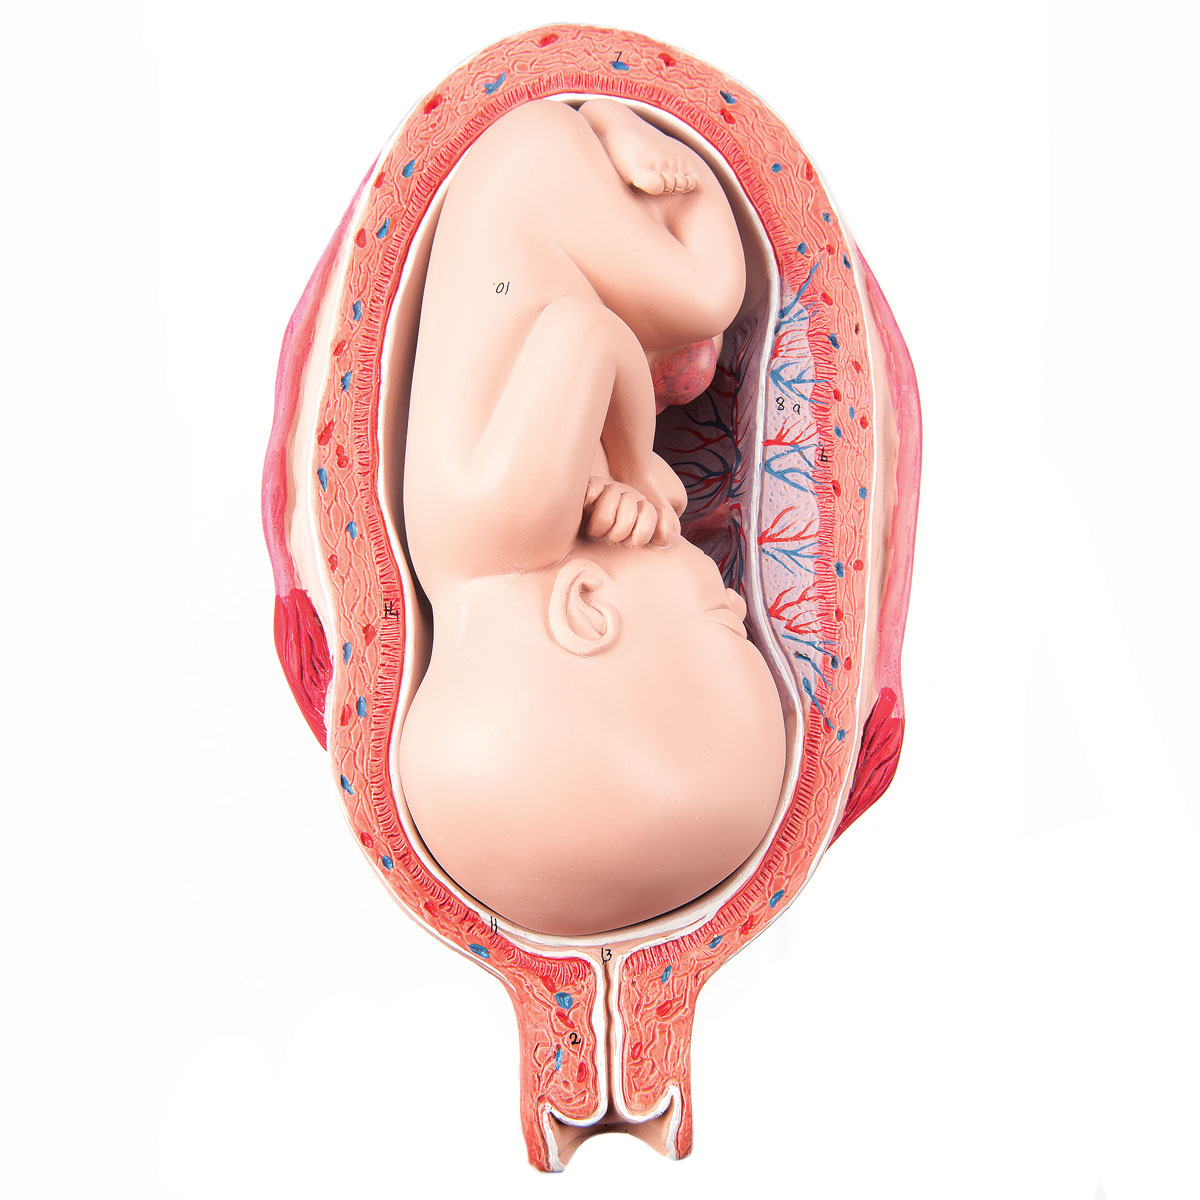

Во время беременности, положение плода имеет большое значение для мамы и малыша. Одним из типичных положений является продольное предлежание головное. В этом положении голова малыша находится внизу, а ножки - наверху. Это положение достаточно распространено и предпочтительно для естественных родов.

Расположениребенка в матке

Плод лежит головой вниз

Расположение ребенка в матке

Ребенок вниз головой в животе

Плод лежит головой вниз

Longitudinal Lie and Cephalic position of child

Внутриутробный плод и плацента

Фото положения плода во время беременности

Ниже приведены несколько фотографий, которые помогут вам визуализировать положение плода во время беременности.